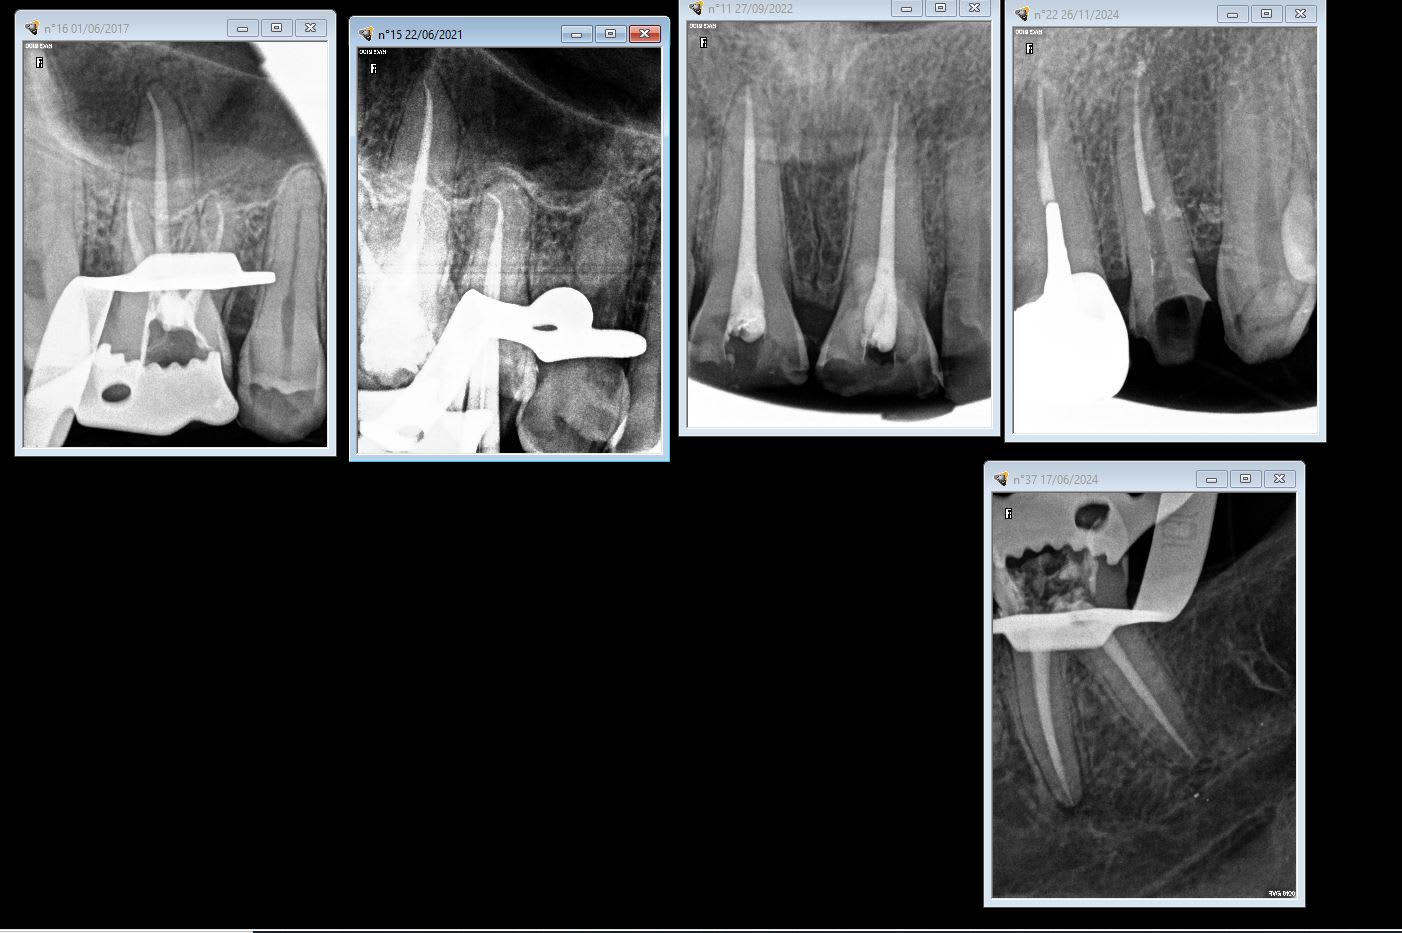

patient pris au hasard toutes les endos que j'ai faites sur ce patient.

> patient pris au hasard toutes les endos que j'ai faites sur ce patient.